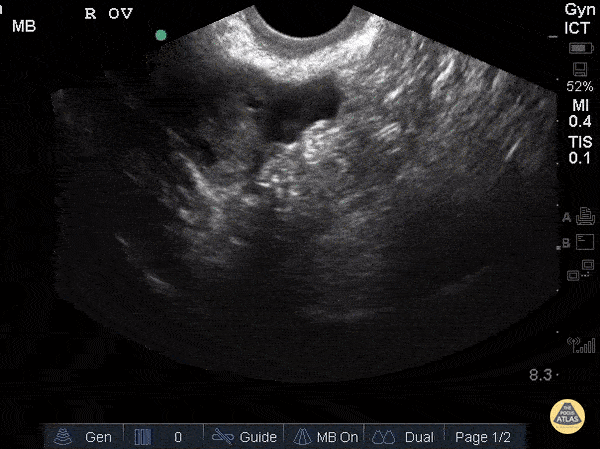

Nulliparous patient. Sukh Singh, MD

https://www.thepocusatlas.com/obgyn